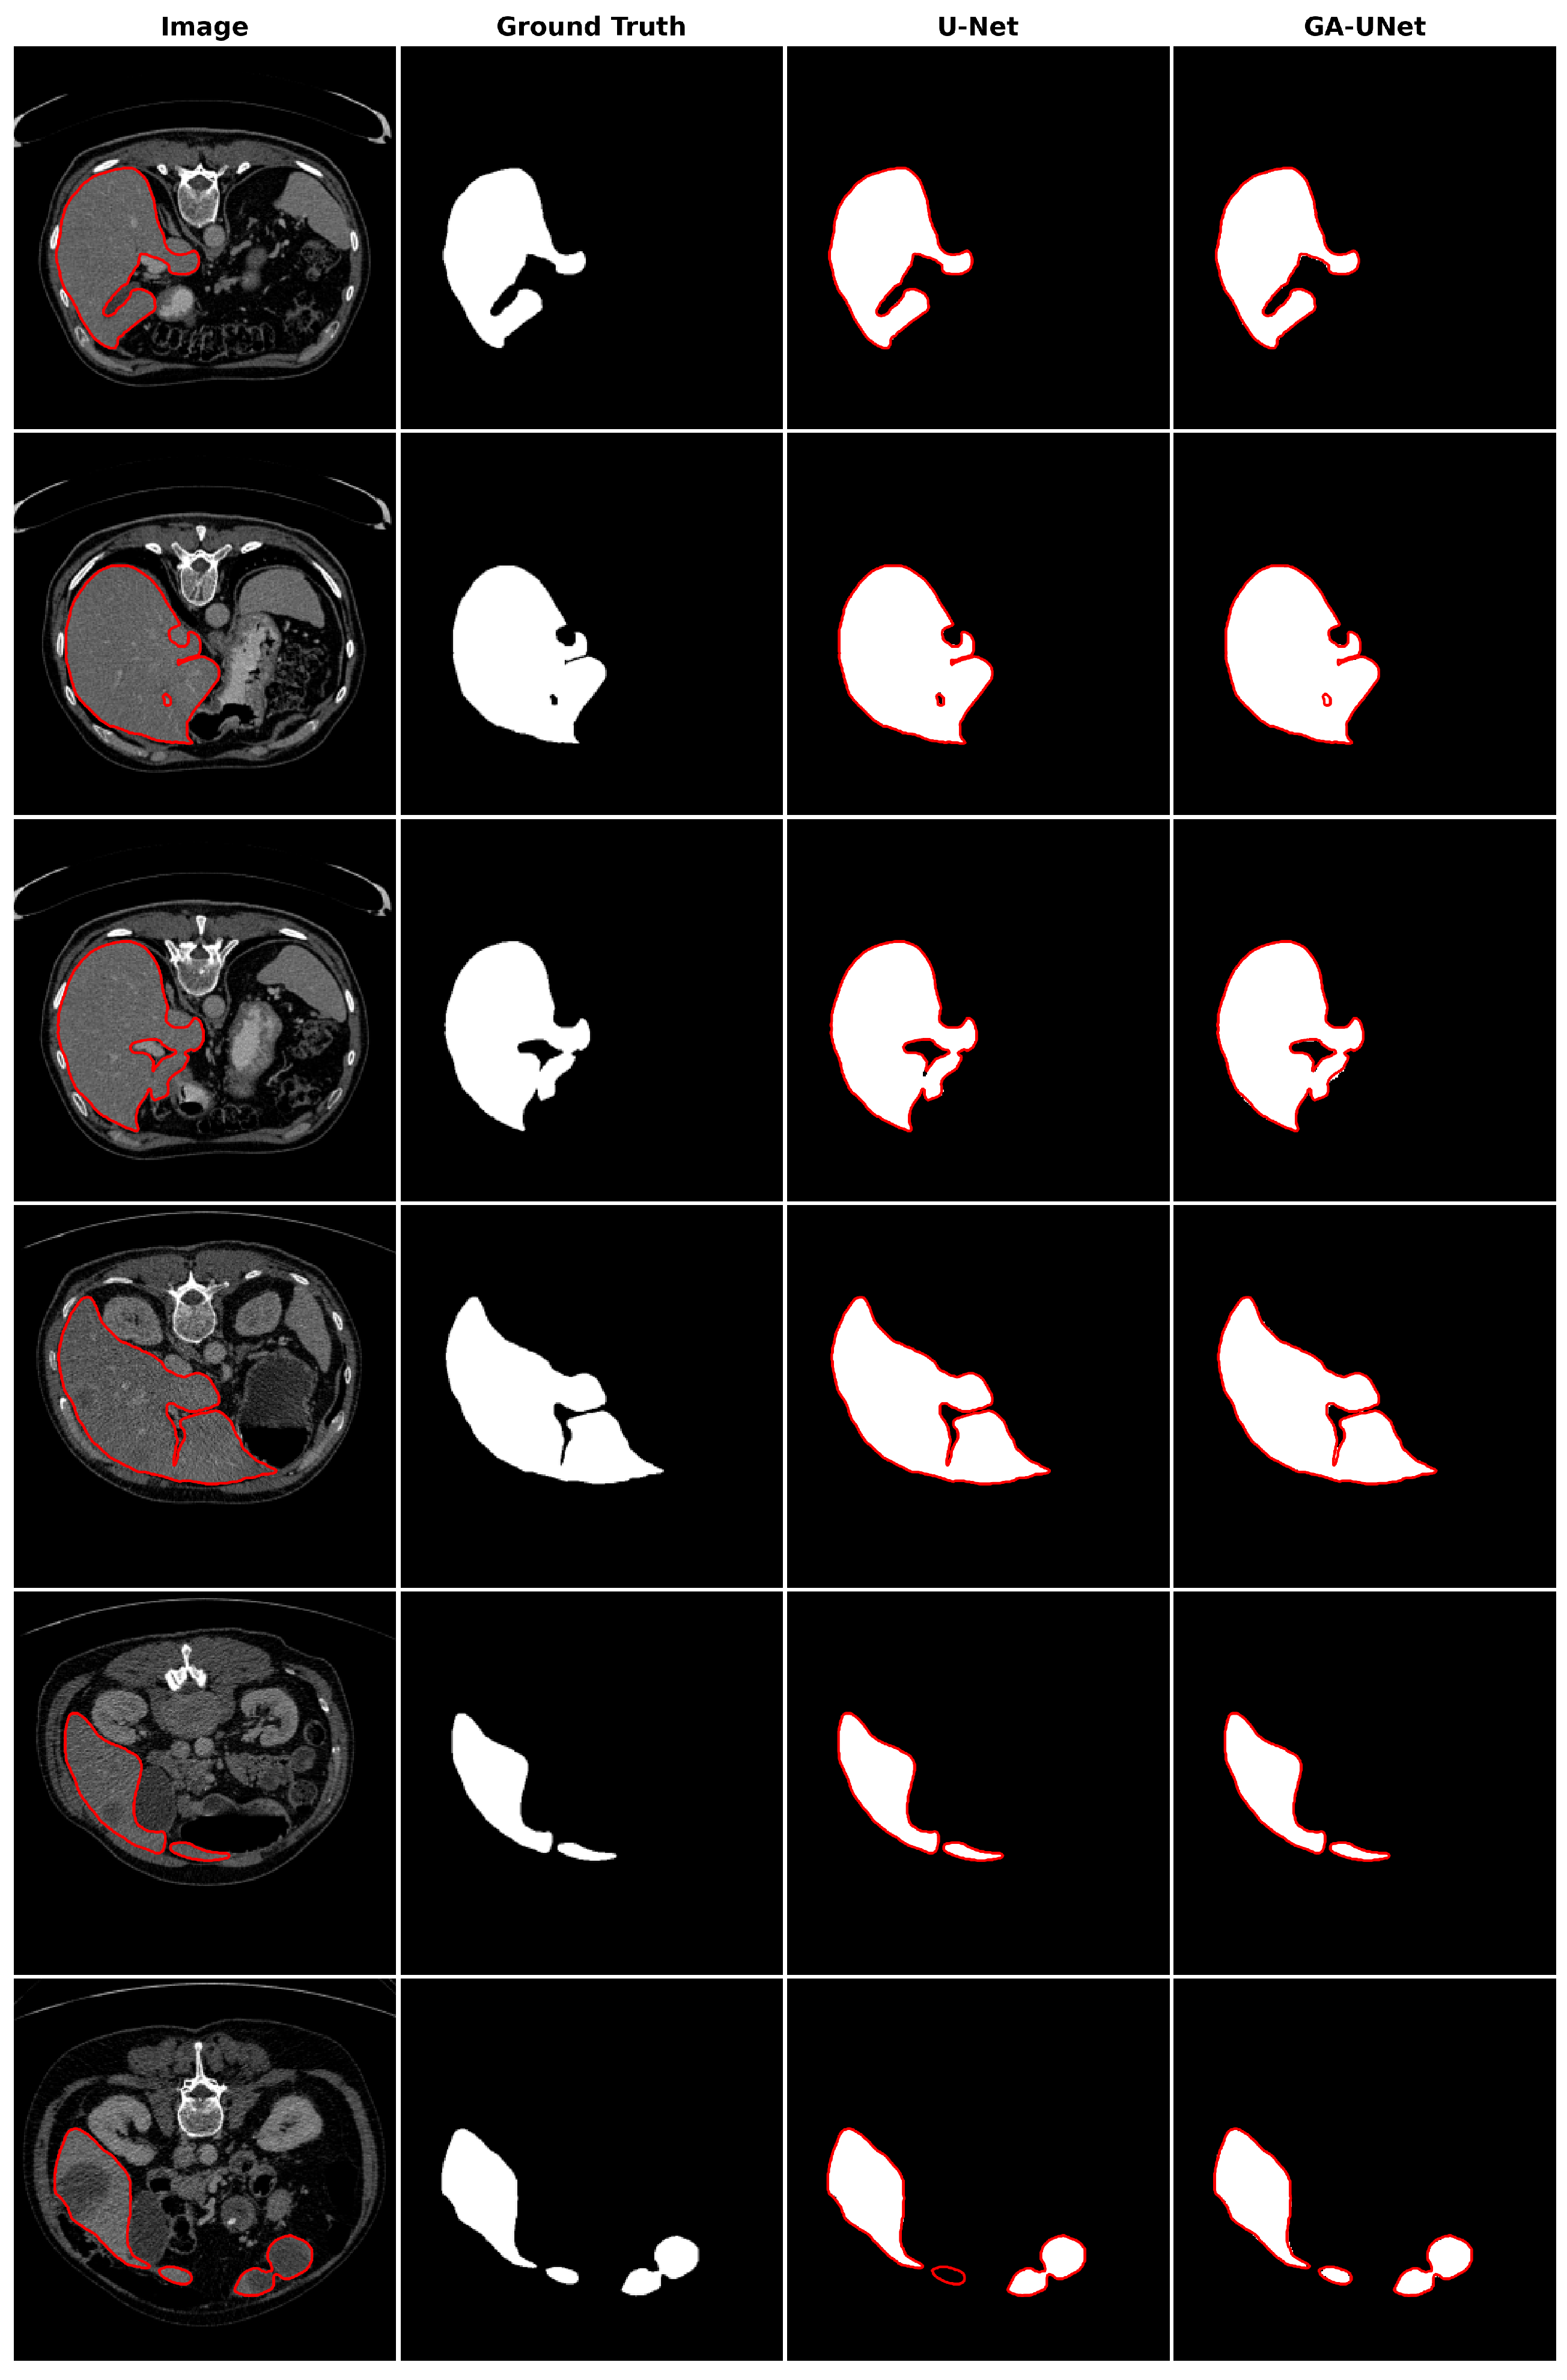

In the qualitative analysis, Figure 13 displays the liver segmentation outcomes obtained from our proposed approach, GA-UNet, compared to those from the original U-Net [12] model, providing a clear visual representation of the results. As demonstrated in Figure 13, the liver segmentation results are considered satisfactory, given that GA-UNet achieved near-complete segmentation of the livers in the scan images. However, as observed in rows 2 and 3, there were instances where a small portion of the liver was missed. On the other hand, in row 6, GA-UNet exhibited better liver segmentation performance than the original U-Net.

Figure 13.

Segmentation results on liver segmentation dataset. From left to right, the columns represent in order: the input image, ground truth, U-Net prediction, and GA-UNet prediction. The red curves represents the actual area of the liver.